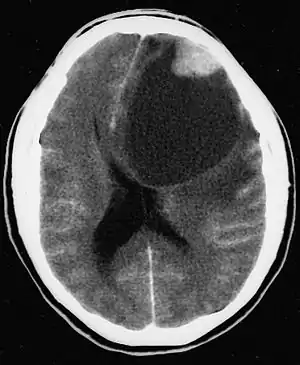

| CT scan of a brain with pleomorphic xanthoastrocytoma. The classic radiographic appearance is one of a superficially situated tumor, here a mural nodule, associated with an underlying cyst. | |

- A CT scan of the brain, and/or an MRI scan of the brain and spine, will be performed. A special dye may be injected into a vein before these scans to provide contrast and make tumors easier to see.